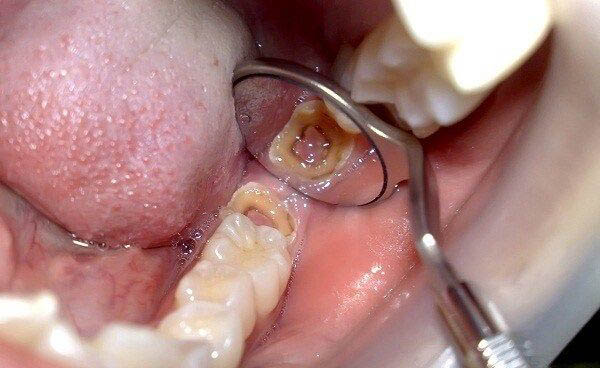

Về kích thước, răng khôn thường nhỏ hơn và ít phát triển đầy đủ hơn so với các răng hàm lớn khác. Bề mặt nhai của răng khôn có nhiều hố rãnh phức tạp, tạo điều kiện thuận lợi cho thức ăn và vi khuẩn tích tụ.

Răng khôn, đặc biệt là răng hàm trên, có bề mặt nhai nhiều hố rãnh sâu và phức tạp hơn so với các răng khác. Những rãnh này có thể tiếp cận lớp ngà răng ngay từ khi mới mọc, làm tăng nguy cơ sâu răng. So với răng hàm lớn thứ nhất và thứ hai, răng khôn có diện tích nhỏ nhưng mật độ hố rãnh cao, tạo nhiều điểm dễ bị vi khuẩn tấn công. Do các rãnh hẹp và sâu, lông bàn chải khó tiếp cận, fluoride trong kem đánh răng khó thẩm thấu, khiến vi khuẩn Streptococcus mutans phát triển mạnh.

Thay đổi màu sắc và hình dạng của răng khôn

Quan sát màu sắc và hình dạng giúp phát hiện răng khôn bị sâu vỡ. Ban đầu, sâu răng xuất hiện dưới dạng đốm trắng đục hoặc nâu nhạt, sau đó chuyển sang nâu đậm hoặc đen, báo hiệu quá trình phá hủy răng. Hình dạng răng cũng thay đổi, với các lỗ nhỏ hoặc rãnh sâu dần mở rộng. Khi sâu nặng, phần thân răng có thể bị vỡ. Khi men răng bị phá hủy, lớp ngà răng vàng lộ ra, gây ê buốt khi ăn đồ nóng, lạnh.